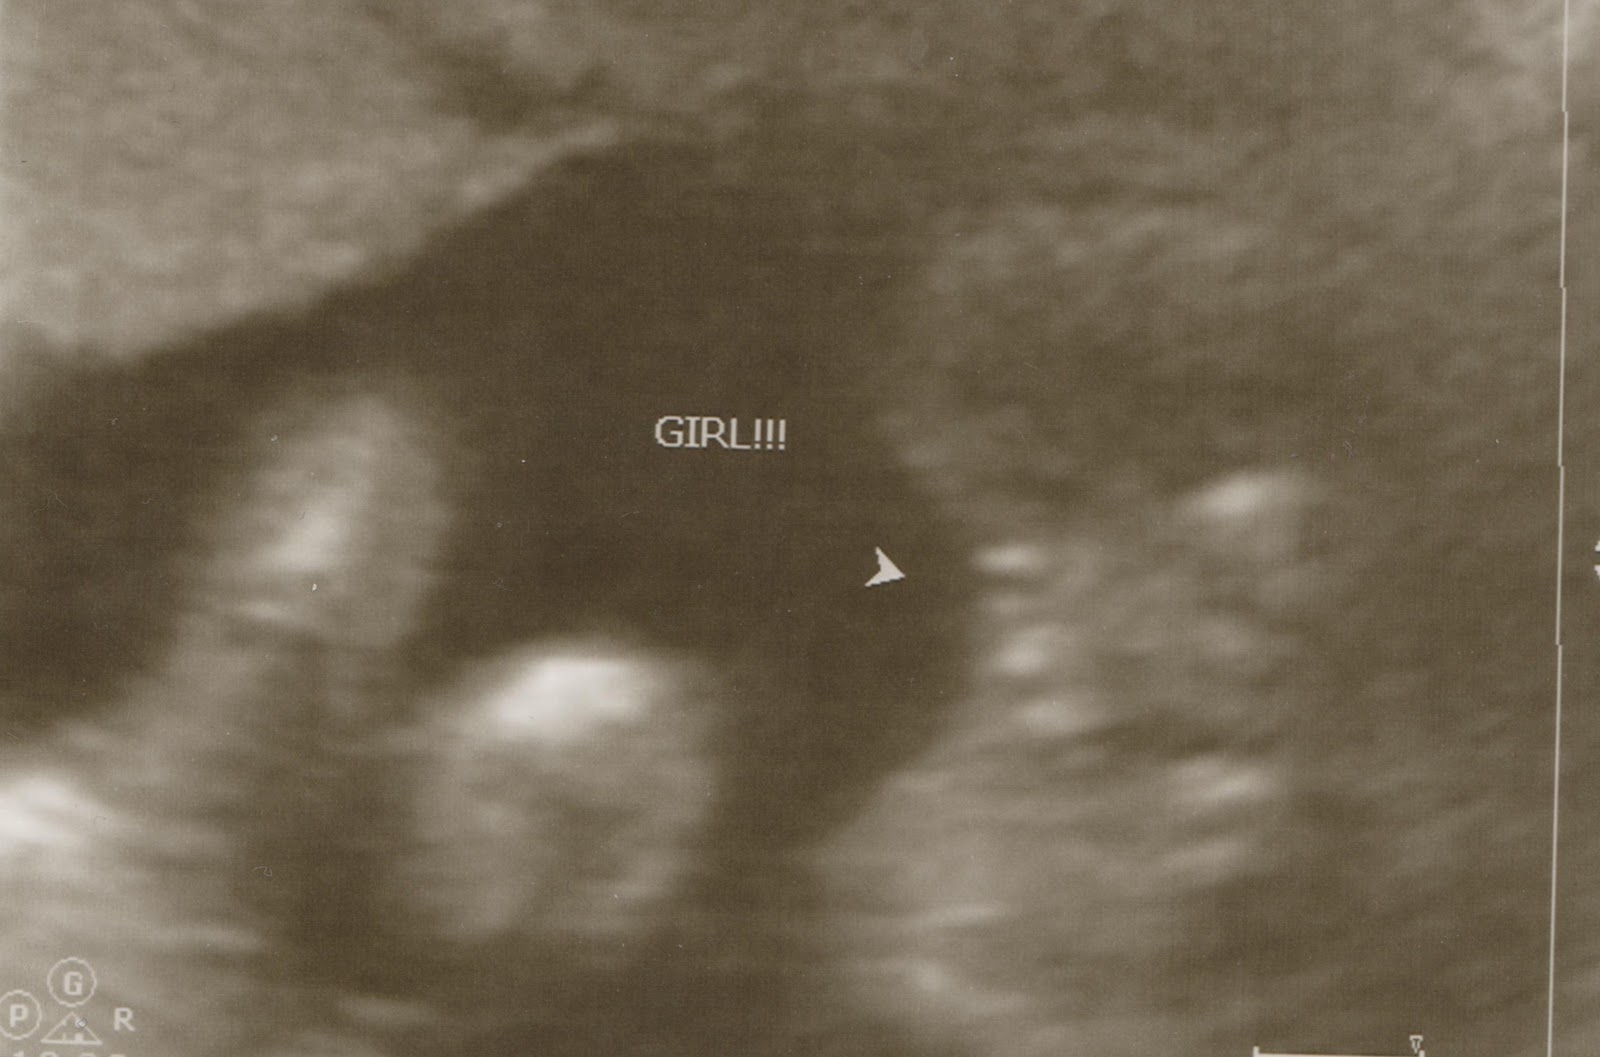

I'll bet you're dying to know how our gender/anatomy scan went, eh? Stick cooperated! And the verdict is . . . dun dun dun . . . she's all girl baby! =] Somewhere between our scan last Tuesday and a few days ago, we finally finished hashing out the name details and I'm proud to say that she also has a name! Brooklyn Leah Harper Olson. And we're already both incredibly in love with her. =]

We were able to walk away from the gender/anatomy scan with two pictures. One is your standard, "It's a girl!" picture and then also one of straight-on shot of her face. =]

The second picture is a little hard to navigate, but just follow the arrow. =] We do have a few more pictures from the ultrasound as well, but I haven't gotten a copy of them quite yet so I'll make a new post as soon as I get them. =]